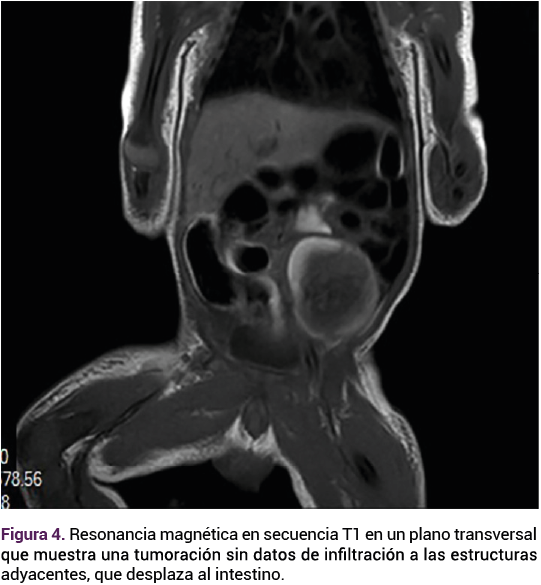

Durante su estancia en la unidad de cuidados neonatales se practicó una resonancia magnética que evidenció la tumoración, sin datos de infiltración a las estructuras adyacentes, que desplaza al intestino. Figura 4.

<strong>Figura 4</strong>

Figura 4.

La ecografía es el principal método diagnóstico para los teratomas testiculares, aunque su efectividad puede verse afectada por la variabilidad en la presentación clínica y la experiencia del operador, lo que puede llevar a un subdiagnóstico.4 En este caso resaltan varios puntos críticos, primero la importancia del seguimiento ecográfico detallado durante el embarazo, que puede facilitar intervenciones quirúrgicas oportunas y mejorar los desenlaces neonatales.6 De este caso puede interpretarse la necesidad del enfoque sistemático, con la incorporación de técnicas adicionales, como la resonancia magnética fetal, que se utiliza como técnica de imagen complementaria a la ecografía prenatal y ha sido validada en la investigación prenatal de las tumoraciones sólidas abdominales, anomalías del aparato gastrointestinal y genitourinario.7

En este caso la resonancia magnética se practicó en el periodo posnatal inmediato. Su protocolo debería incluir, siempre, secuencias potenciadas en T2, para la valoración de la anatomía, y también las potenciadas en T1.7 La resonancia magnética fetal no es de aplicación común para el tamizaje prenatal, aunque con el debido asesoramiento completo de la anatomía fetal su utilidad puede llegar a ser relevante.8 El diagnóstico prenatal puede ayudar en el asesoramiento y la planificación del parto en un entorno con acceso inmediato a la atención multidisciplinaria.8